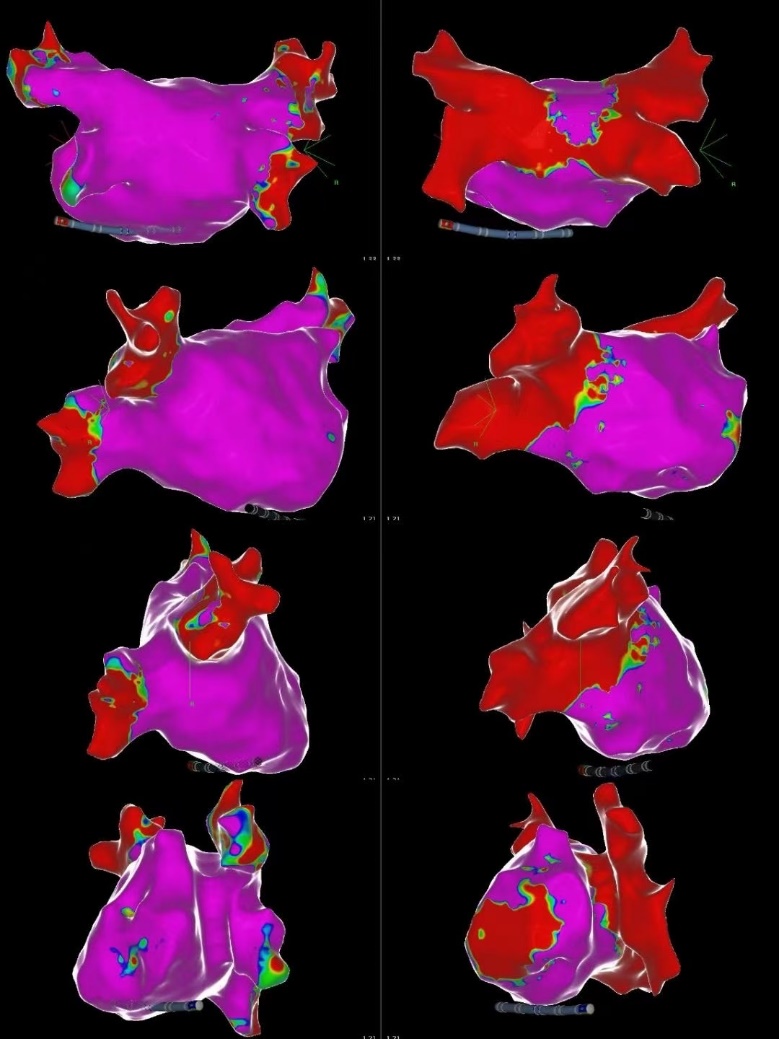

术前术后三维标测对比,肺静脉完美电隔离

手术过程在三维导航系统辅助下精确实施,操作时间短,创伤小,患者术中舒适度高。FARAPULSE系统以非热能方式工作,避免了传统消融可能引起的心房食管瘘、膈神经损伤等并发症,同时确保高效消融效果。术后标测显示,患者肺静脉实现了完全电隔离,手术取得了圆满成功。